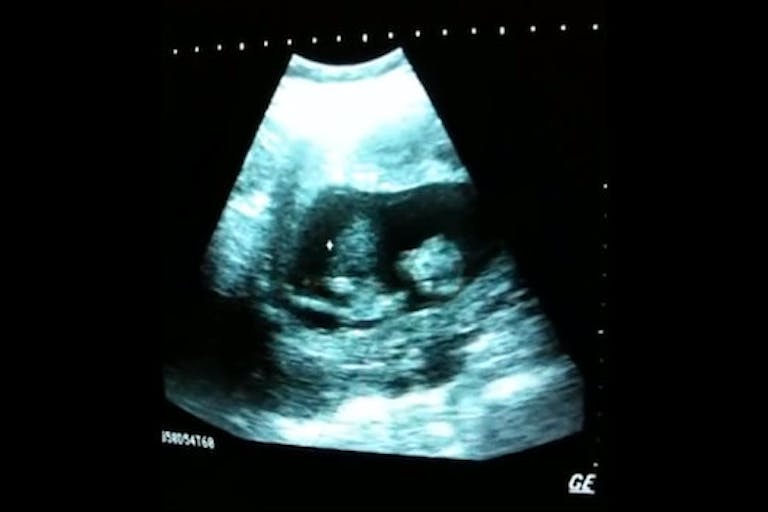

8 to 12 week preborn baby plays in mom’s womb

Those adorable comments were spoken by a young child watching a preborn baby on an ultrasound screen. In this video posted on YouTube, you can see this baby jump and move around in it’s mother’s womb. It’s a powerful image. So powerful in fact, that it currently has over 500,000 views.

I think I was somewhere between 8-12 weeks pregnant because I could not feel her movements. If it wasn’t for the sono, I would not believe it. Thank you, as well. She’s an absolute joy.

How can anyone say that this isn’t a baby? Maybe not a “fully developed” baby ready to be born and able to survive outside of her mother’s womb, but a baby nonetheless. I definitely see much more than just a clump of cells or blobs of tissue…I see life!

As YouTube user Salman Oldipo said, this baby “is a complete human being.” According to the mother, the baby is also a girl who is still full of spunk.